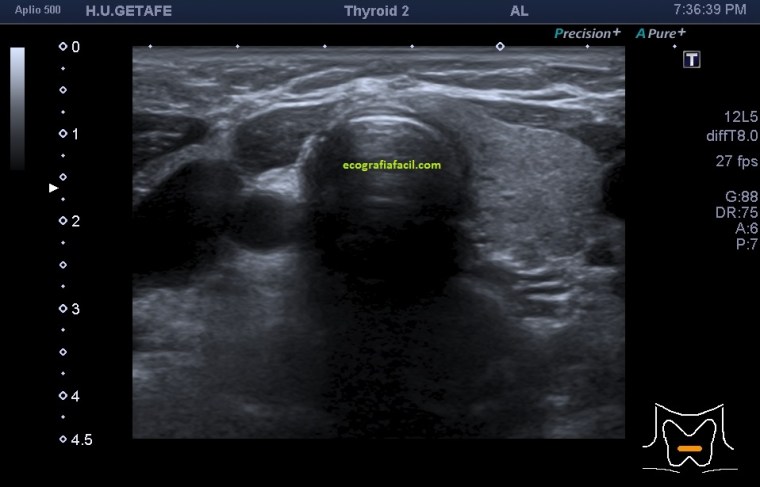

Cuando realizamos una exploración tiroidea, lo que nos encontramos cuando iniciamos el estudio es esta imagen, es la imagen que debemos buscar para comenzar y hacernos una composición de lugar. En este caso, la imagen número 1 es una imagen con semiología de normalidad donde vemos ecoestructuras normales típicas de dicha localización anatómica en un corte axial o transverso del cuello donde nos indica el pictograma.